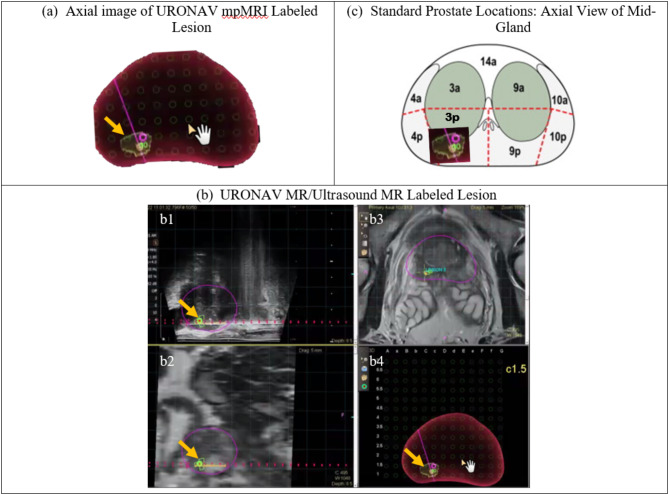

Purpose: The prevalence of prostate cancer (PCa) necessitates advanced diagnostic approaches for detection and lesion characterization. Utilizing two patient cohorts (n = 85), this study analyzes a custom-designed 3D ultrasonic acoustic radiation force impulse (ARFI) elasticity imaging system alongside an Index of Suspicion (IOS) lesion ranking system to evaluate reader sensitivity, positive predictive values, inter-reader reliability, and ARFI-mpMRI concordance. The IOS system provides standardized criteria for lesion assessment, enabling consistency in stratifying PCa lesion suspicion.

Materials and methods: Three readers were trained on multiparametric ultrasound (mpUS) (combined ARFI and B-mode) prostate image volumes from 6 patients based on the IOS criteria. The readers then marked suspicious lesions in 79 patients who were retrospectively compared with histopathology-identified (Cohort I, post-radical prostatectomy) or biopsy-confirmed (Cohort II) cancerous regions.